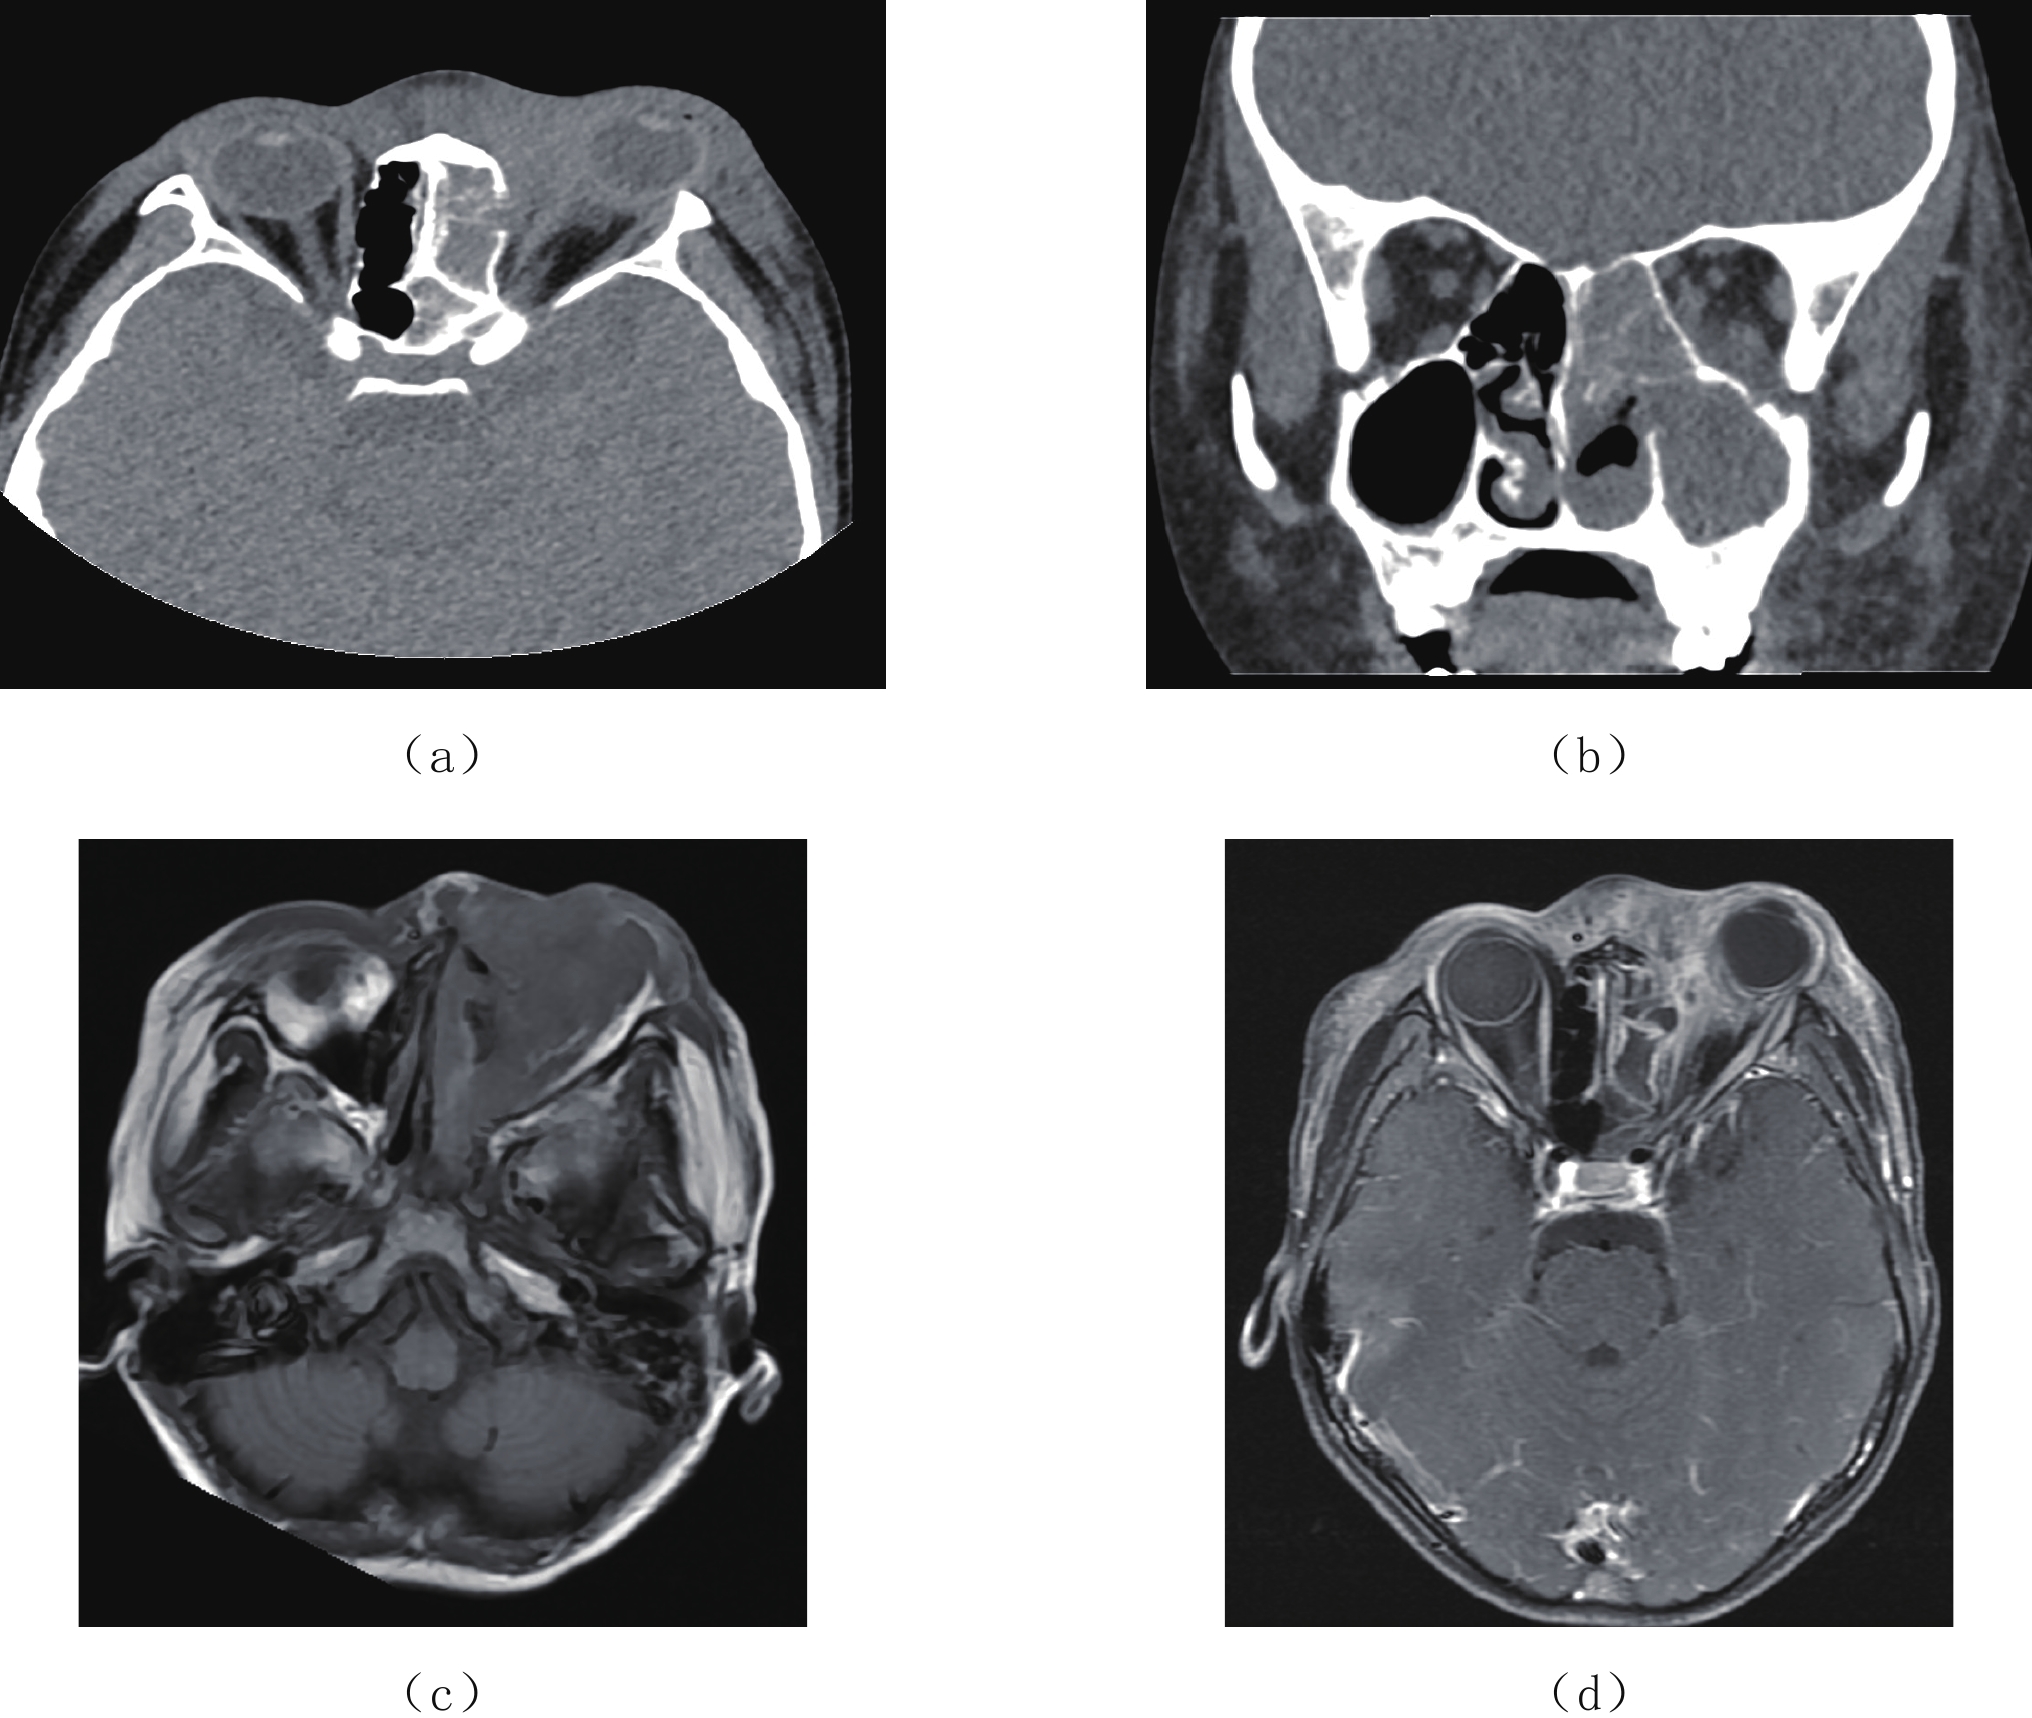

Epstein-Barr virus (EBV), also known as a gamma herpesviru, has the characteristics of lymphophilic tissue. EBV is one of the most common human viruses of the human cold virus group and the first human tumor virus found. Infection with EBV occurs by the oral transfer of saliva and respiratory secretions. Human B-lymphocytes and epithelial cells are EBV-susceptible host cells. First EBV infection often occurs in infancy and in childhood. EBV-associated diseases include infectious mononucleosis, EB virus associated hemophagocytic lymphoproliferative disorder (EBV-HLH), chronic active EBV Infection, EBV infection-associated autoimmune disease. EBV infection can also cause the proliferative diseases of the infected cells, such as various non-malignant lymphoproliferative diseases, lymphomatoid granulomatosis, EBV associated with many more malignant diseases including Burkitt′s lymphoma, Hodgkin′s lymphoma, Diffuse Large B-Cell Lymphoma, NK/T cell lymphoma, nasopharyngeal carcinoma, a subset of gastric carcinomas, and many more. This paper mainly focuses on EBV associated lymphoproliferative diseases and imaging characteristics in children.